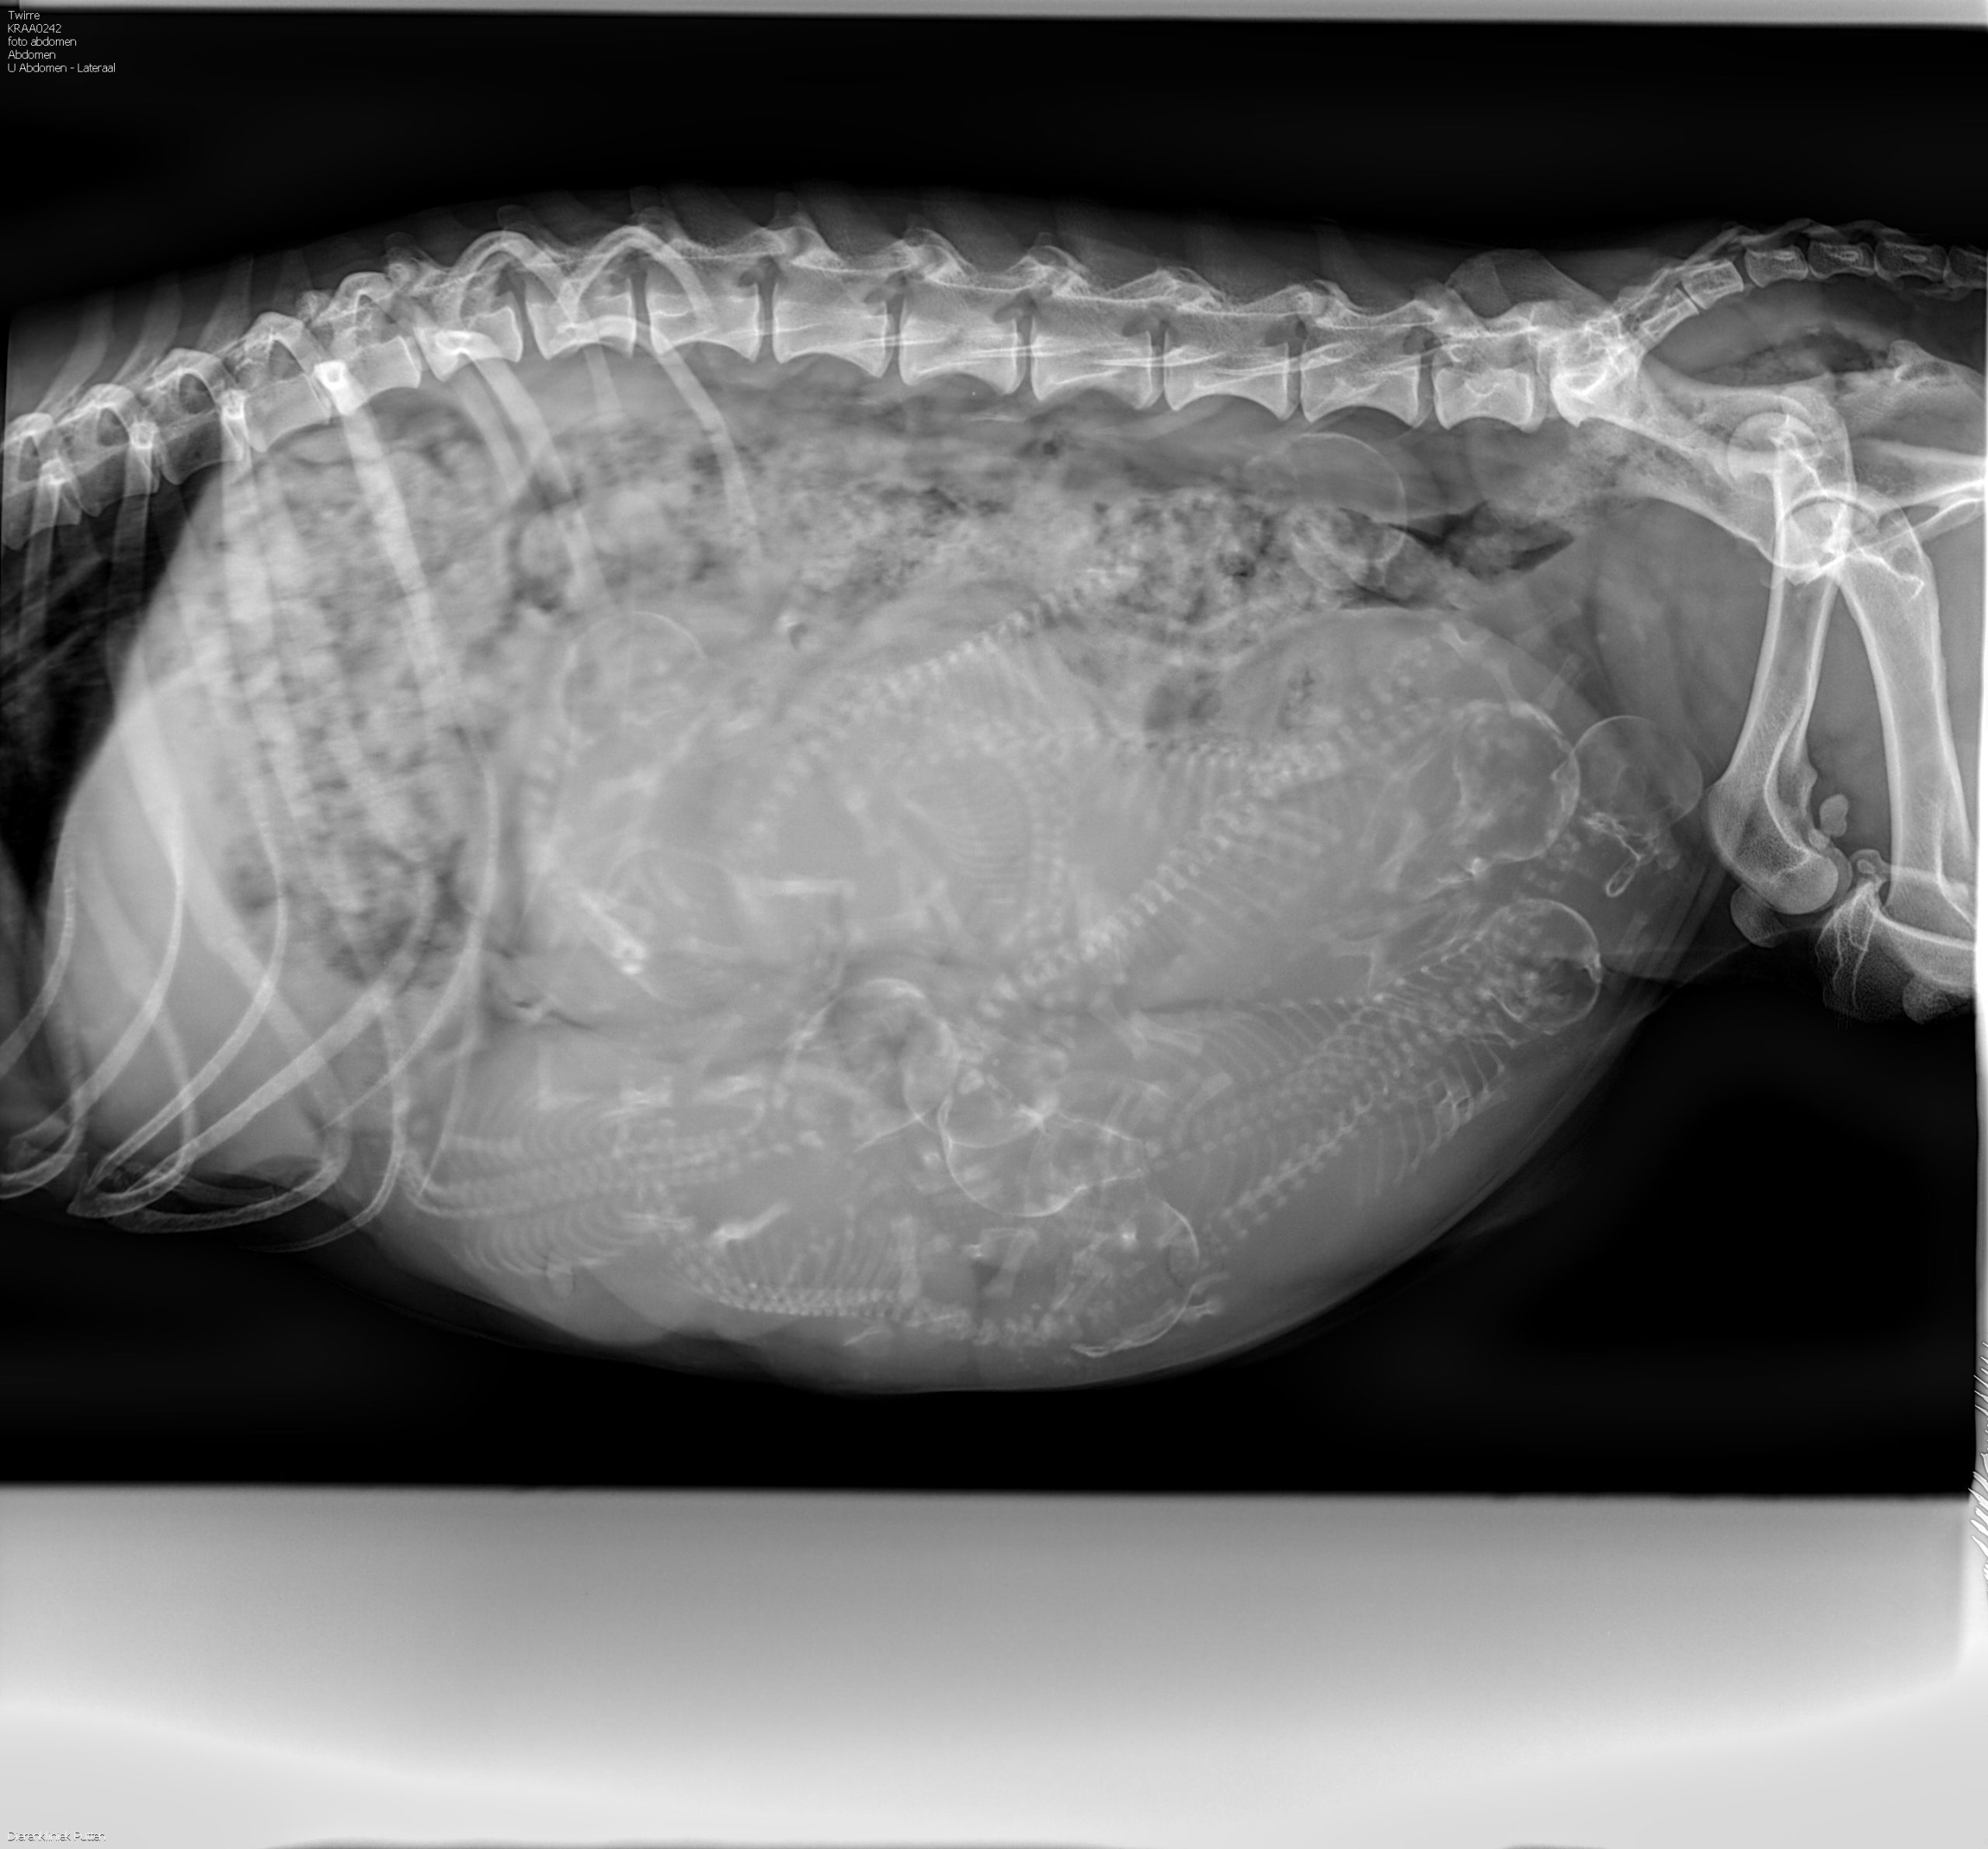

Bayerischer Gebirgsschweisshunden puppies born 19/08/2022. 3 males en 4 females. Mother Pleun (Bernis Van Jagthuis Gerven) and father Abe ( Swawir Sfora Nemroda) regularly used for tracking owned by Herwi Hoenink kennel Van t’Rutbekerveld. All puppies have a new owner.